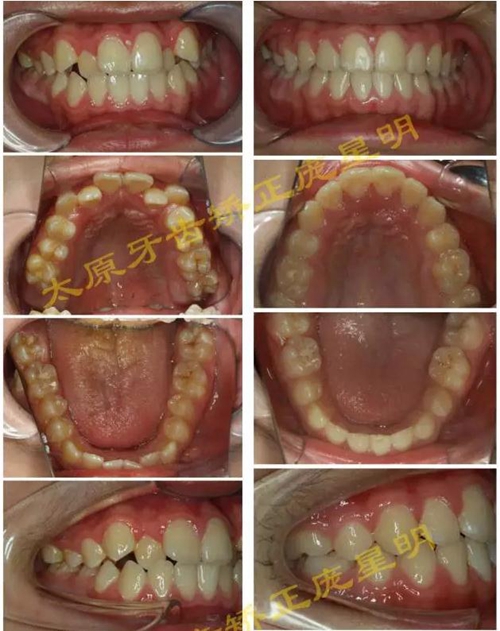

1500865770_445373.jpg1500865976_358577.jpg

此病例主要考慮的是擁擠度,磨牙及尖牙關(guān)系,前牙覆合覆蓋,生長(zhǎng)潛力和智齒。